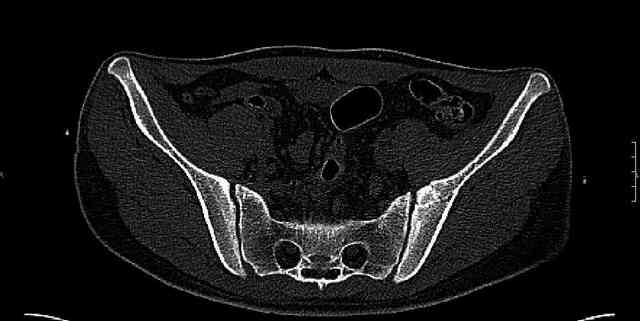

The last two images from the 3-D CT scan certainly makes the fracture look worse than the plan radiographs.

The joint is non-concentric as the head appears to be either "following the caudal segment", or the dome component is displaced from the tethered head... or so it seems... and he's young... so, many fracture surgeons would recommend reduction and fixation.

Some more images. Does it help to guess which part of the acetabulum is displaced?

Normal appearing SI joints and a healed posterior column limb... my bet's on caudal segment displacement.